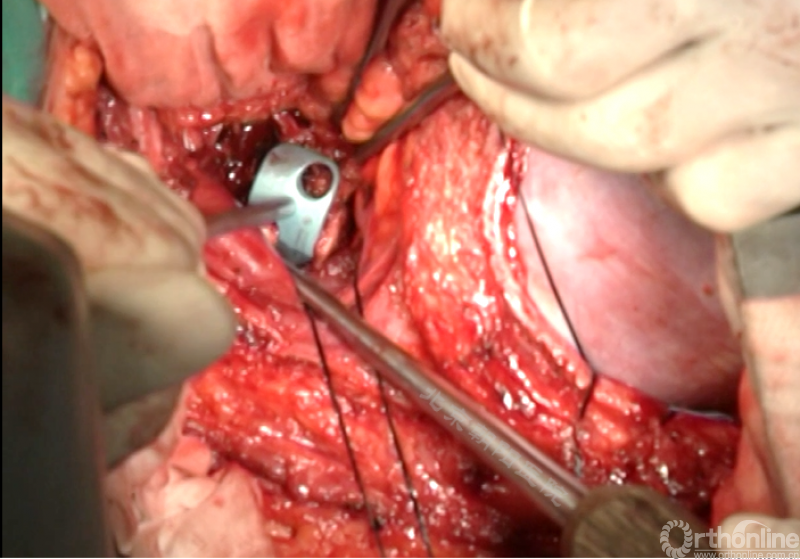

内固定选择的是5.5mm双棒系统,先置入顶椎的螺钉垫板。

置入顶椎的椎体螺钉,螺钉可置入椎体中部到后方1/3之间的范围内。

使用双棒系统时,先置入背侧的螺钉,螺钉指向椎体中线,后置入腹侧的螺钉,螺钉轻度指向后侧。形成对椎体的三角形抓持力。

胸腔侧、腹腔侧螺钉全部置入后,骨移植物植人的越靠近后纵韧带或者纤维环的后缘越好。

将预先折弯的金属棒先置入背侧。

椎间融合器经前方置入凹侧,确保腰椎前凸的恢复和冠状面畸形的矫正,将剩下的骨移植物置入椎间隙内。

置入腹侧金属棒。

使用双棒系统时先安装背侧的棒,可进行90°的去旋转,也可以直接通过前方螺钉矫正冠状面和矢状面的畸形,然后固定后方的棒,可进一步通过加压矫正冠状面畸形。

矫正后神经检测未见异常术中唤醒患者下肢活动良好,术中透视矫正效果满意、内固定位置良好。根据手术具体情况放置合适尺寸的横连接加强内固定。